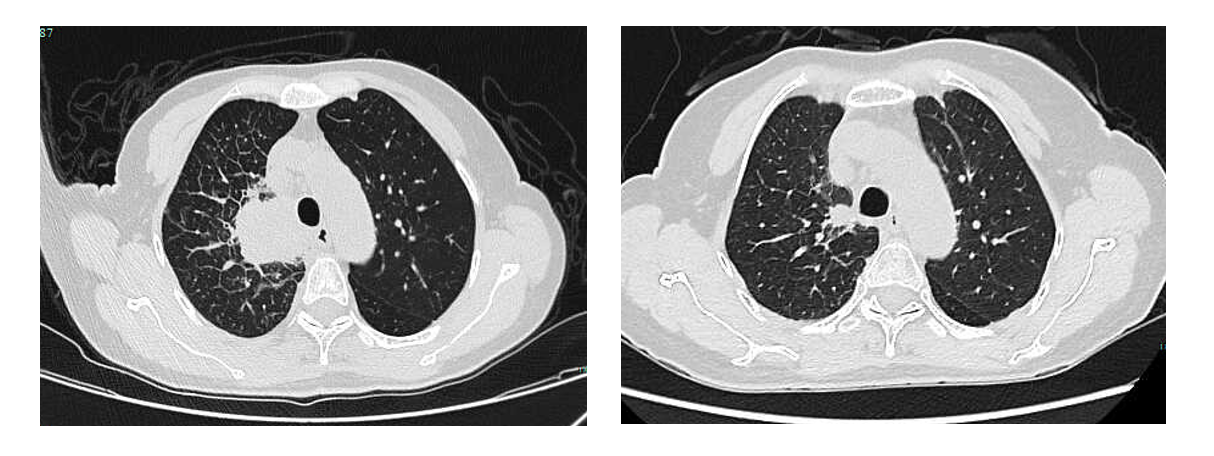

疗效评价:治疗仅1月余,2024年5月7日第一次疗效评估即达到部分缓解(PR),病灶较治疗前显著缩小(图1),治疗应答迅速且强效2024年7月31日第三次疗效评估仍维持PR状态,病灶在首次缩小的基础上持续退缩(图2),肿瘤负荷进一步降低。2026年1月13日最近一次肿瘤评估提示病灶接近CR(图2)。截止随访,患者已接受芦康沙妥珠单抗治疗22个月,PFS达22个月,疾病控制持续稳定,未出现进展迹象,实现了长期高质量生存。

图1. 2024年3月19日(左)对比2024年5月7日(右)